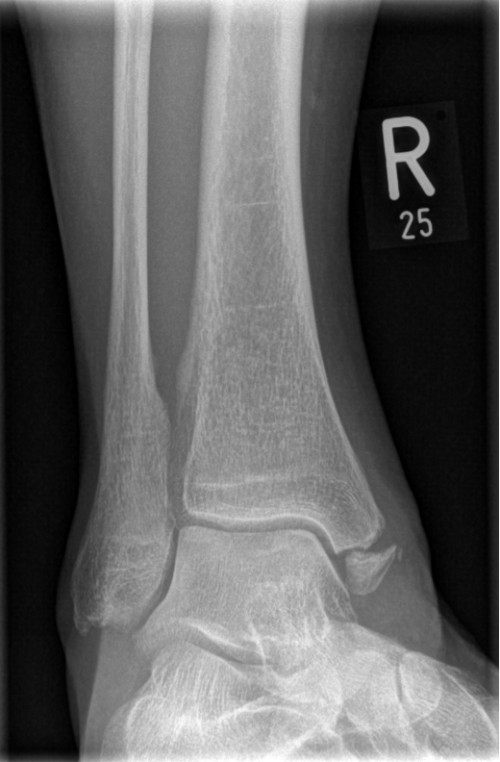

ICD: S82.5

Eine 66-jährige Patientin stellt sich in der Notfallambulanz vor und berichtet von einer Leiter gestürzt zu sein. Sie habe für ihren Enkel Lego-Spielzeug vom Dachboden holen wollen und sei dabei von der Leiter gerutscht. Sie sei auf ihren beiden Fersen gelandet und anschließend auf den Rücken gefallen. Der linke Fuß sei seitdem nicht belastbar, der rechte Fuß schon. Am rechten Fuß sei jedoch eine Schwellung im Bereich der Sprunggelenke sichtbar geworden.